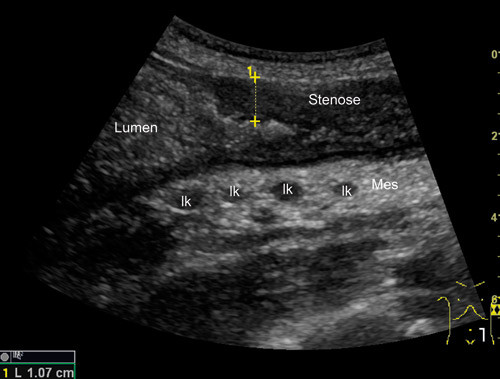

Stenoser kan forekomme ved Crohns sykdom (fig 3). Man ser da ofte betydelig fortykket vegg og avsmalnet lumen og en prestenotisk utvidelse. Den fortykkede tarmveggen i stenosen har liten eller ingen motilitet. Bortfall av lagdeling i stenosen indikerer ødem i tarmveggen og sannsynlig akutt inflammasjon, mens mer bevart lagdeling kan indikere fibrose (18). Det er viktig for valg av behandling å vite om den fortykkede veggen i en stenose skyldes hovedsakelig aktiv inflammasjon eller fibrose. Ved aktiv inflammasjon kan pasienten ha nytte av medisinsk behandling, mens kirurgi vanligvis er indisert ved kroniske betennelsesforandringer og fibrose (18). Hvis man ved hjelp av fargedoppler ser rikelig med kar i stenoseområdet, tolkes det som et uttrykk for inflammatorisk aktivitet. Da kan medikamentell behandling være verdt å forsøke. Ultralyd er i flere studier brukt til å påvise stenoser hos pasienter med Crohns sykdom. I disse studiene har ultralyd en sensitivitet på 74 – 100 % og en spesifisitet på 91 – 100 % (9, 14, 19).